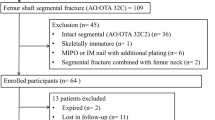

Between January 2012 and December 2017, 212 patients with the initial diagnosis of an acute subtrochanteric femoral fracture were treated at our level 1 trauma centre by femoral nailing. A review of the radiographs revealed that 91 fractures were either intertrochanteric fractures with subtrochanteric fracture extensions or proximal femoral shaft fractures and thus did not meet the strict definition of subtrochanteric fractures, which we applied for this study [9, 10, 19]. Of the remaining 121 patients, 47 were excluded from the study due to incomplete radiological follow-up, subsequent treatment in an external hospital or death during the follow-up period in geriatric patients. A total of 74 patients were therefore included in this study. There were 47 females and 27 males. Patients’ mean age was 70.2 ± 16.6 years (23–96 years).